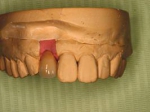

インセラム(オールセラミック)症例①

治療前治療前インセラム(オールセラミック)冠による修復。 主訴は前歯が汚い 金属を使わないオールセラミックでの治療を勧めた。 術前 治療後治療後術後